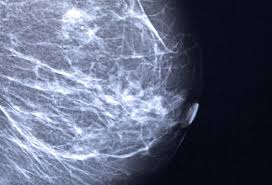

Mammogram Images Normal And Abnormal from www.verywellhealth.com Any area that does not look like normal tissue is a possible cause for concern. Dense breast tissue appears solid. A diagnostic mammogram is used to check for breast cancer when there is a sign or symptom of disease. They are not usually related to cancer. Your doctor will note if they have changed over time. If you've had a mammogram before, the radiologist should compare your old mammogram to the new one to look for changes. A lump or tumor will show up as a focused white area on a mammogram. It can be hard to know from a mammogram image whether the cluster is dcis or invasive breast cancer.

The harmless nature of ultrasound machines also make them a benefit to patients. These deposits show up as tiny white spots on a mammogram, and there may be only one or two, or too many to count, says jay baker, md, a breast imaging specialist at the duke cancer center. Tumors may be benign or cancerous. If you've had a mammogram before, the radiologist should compare your old mammogram to the new one to look for changes. Breast cancer and some noncancerous (benign) breast conditions can appear white on a mammogram.

While it is useful to know what cysts and tumors look like in an ultrasound image, always rely on the insight of an experienced doctor or radiologist when. The look of breast cancer on a mammogram a tumor or lump will appear as a focused white area on the mammogram. The photographs included on this page are the results of reconstructive procedures performed by the surgeons at the center for restorative breast surgery. Any area that does not look like normal tissue is a possible cause for concern. A mammogram can show breast changes such as calcifications, masses, or other symptoms that might be cancer. During a breast exam, your doctor looks for visual changes and uses their fingers to feel for lumps. They are usually benign (not cancer). Inflammatory breast cancer affects breast tissue and can appear unusually dimpled or thick. • microcalcifications are small and may appear in clusters. Dulce corazon the transfer of estrogen from a mother to her newborn child may cause breast lesions on the child. Most people assume that what doctors are looking for on a mammogram are lumps, dr. The doctor reading your mammogram will be looking for different types of breast changes, such as small white spots called calcifications, larger abnormal areas called masses, and other suspicious areas that could be signs of cancer. The following images show what cancer looks like on an ultrasound.

Generally speaking, the denser the tissue, the whiter it appears. The harmless nature of ultrasound machines also make them a benefit to patients. Mammograms may show suspicious areas of the breast, white spots, and microcalcifications. Lobular carcinoma) are more difficult to detect than. While it is useful to know what cysts and tumors look like in an ultrasound image, always rely on the insight of an experienced doctor or radiologist when. People should become familiar with the typical look and feel of their. (a cluster of microcalcifications can also be a benign finding on a mammogram. Most people assume that what doctors are looking for on a mammogram are lumps, dr. There are few risks associated with mammography. You can tell they are solid due to their grey color. On the body, a lesion is an area with is an abnormality or alteration in the tissue's integrity. According to the american cancer society (acs), the most common sign of breast cancer is a new lump or mass in the breast. This has an odd shape and grey color.